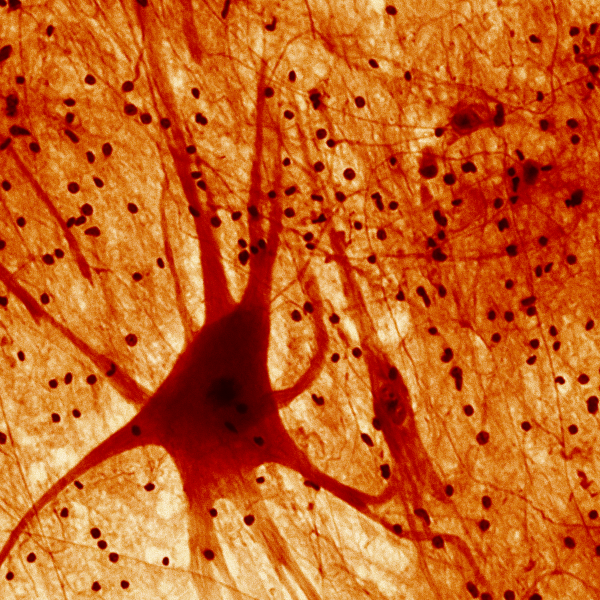

Neurological and Mental Health Conditions

Blood testing helps map the physiology of CFS/ME—stress signaling, inflammation, nutrient status, and protein balance. At Superpower, we test Cortisol, hs-CRP, Vitamin D, and Albumin. We offer in-clinic and at-home blood testing; home collection for CFS/ME is currently available in selected states. (See FAQs below for more info).

Blood testing helps reveal chronic stress’s impact on your neuroendocrine and immune systems. At Superpower, we measure cortisol, DHEAS, and hs-CRP to map HPA-axis activity and inflammation. We offer in-clinic and at-home testing; home kits are currently available in selected states. (See FAQs below for more info).

Blood testing clarifies vascular drivers of cognitive decline. At Superpower, we measure LDL, ApoB, Lp(a), and hs-CRP to profile atherogenic burden and inflammation for Vascular Dementia risk. We offer in-clinic and at-home testing; home kits are available in selected states. (See FAQs below for more info).

Depression often reflects shifts in stress hormones, inflammation, and immune balance. Blood testing grounds symptoms in biology. At Superpower, we test Cortisol, hs-CRP, and NLR to profile these systems. We offer in-clinic and at-home testing; home collection is currently available in selected states. (See FAQs below for more info).

Assessing sarcopenia with blood testing clarifies muscle health drivers—anabolic signaling, androgen status, and protein nutrition (IGF-1, testosterone, albumin). At Superpower, we offer IGF-1, Testosterone, and Albumin testing, in-clinic and at home. Home testing is currently available in selected states. (See FAQs below for more info).